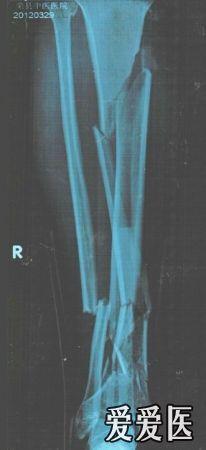

胫骨多段骨折,请大家指点一下,如何选择内固定

辅助检查:拍片:胫骨多段骨折

初步诊断:胫骨多段骨折

诊断依据:拍片:胫骨多段骨折

讨论内容:胫骨多段骨折,请大家指点一下,如何选择内固定胫骨多段骨折,请大家指点一下,如何选择内固定。